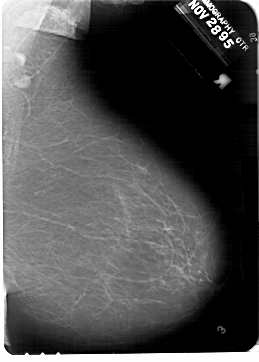

A_1332_1.LEFT_MLO

LEFT_MLO LINES 6871 PIXELS_PER_LINE 5251 BITS_PER_PIXEL 12 RESOLUTION 43.5 OVERLAY